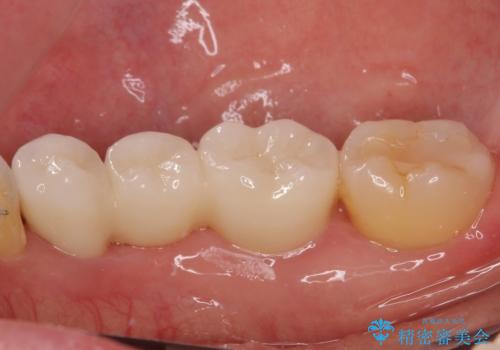

- 上下前歯のデコボコと奥歯の欠損を気にして来院された患者様です。

右下の欠損分は奥歯が倒れ込んでスペースがなくなっていたため、矯正治療により本来の位置に歯を移動させ、オールセラミックブリッジによる欠損補綴治療を行うこととしました。

右下は移動量が多いため、十分な移動が達成されない場合はワイヤー装置を使用する予定としておりましたが、しっかりとマウスピースを装着してくださったため、前歯とともに十分に歯を動かすことができました。